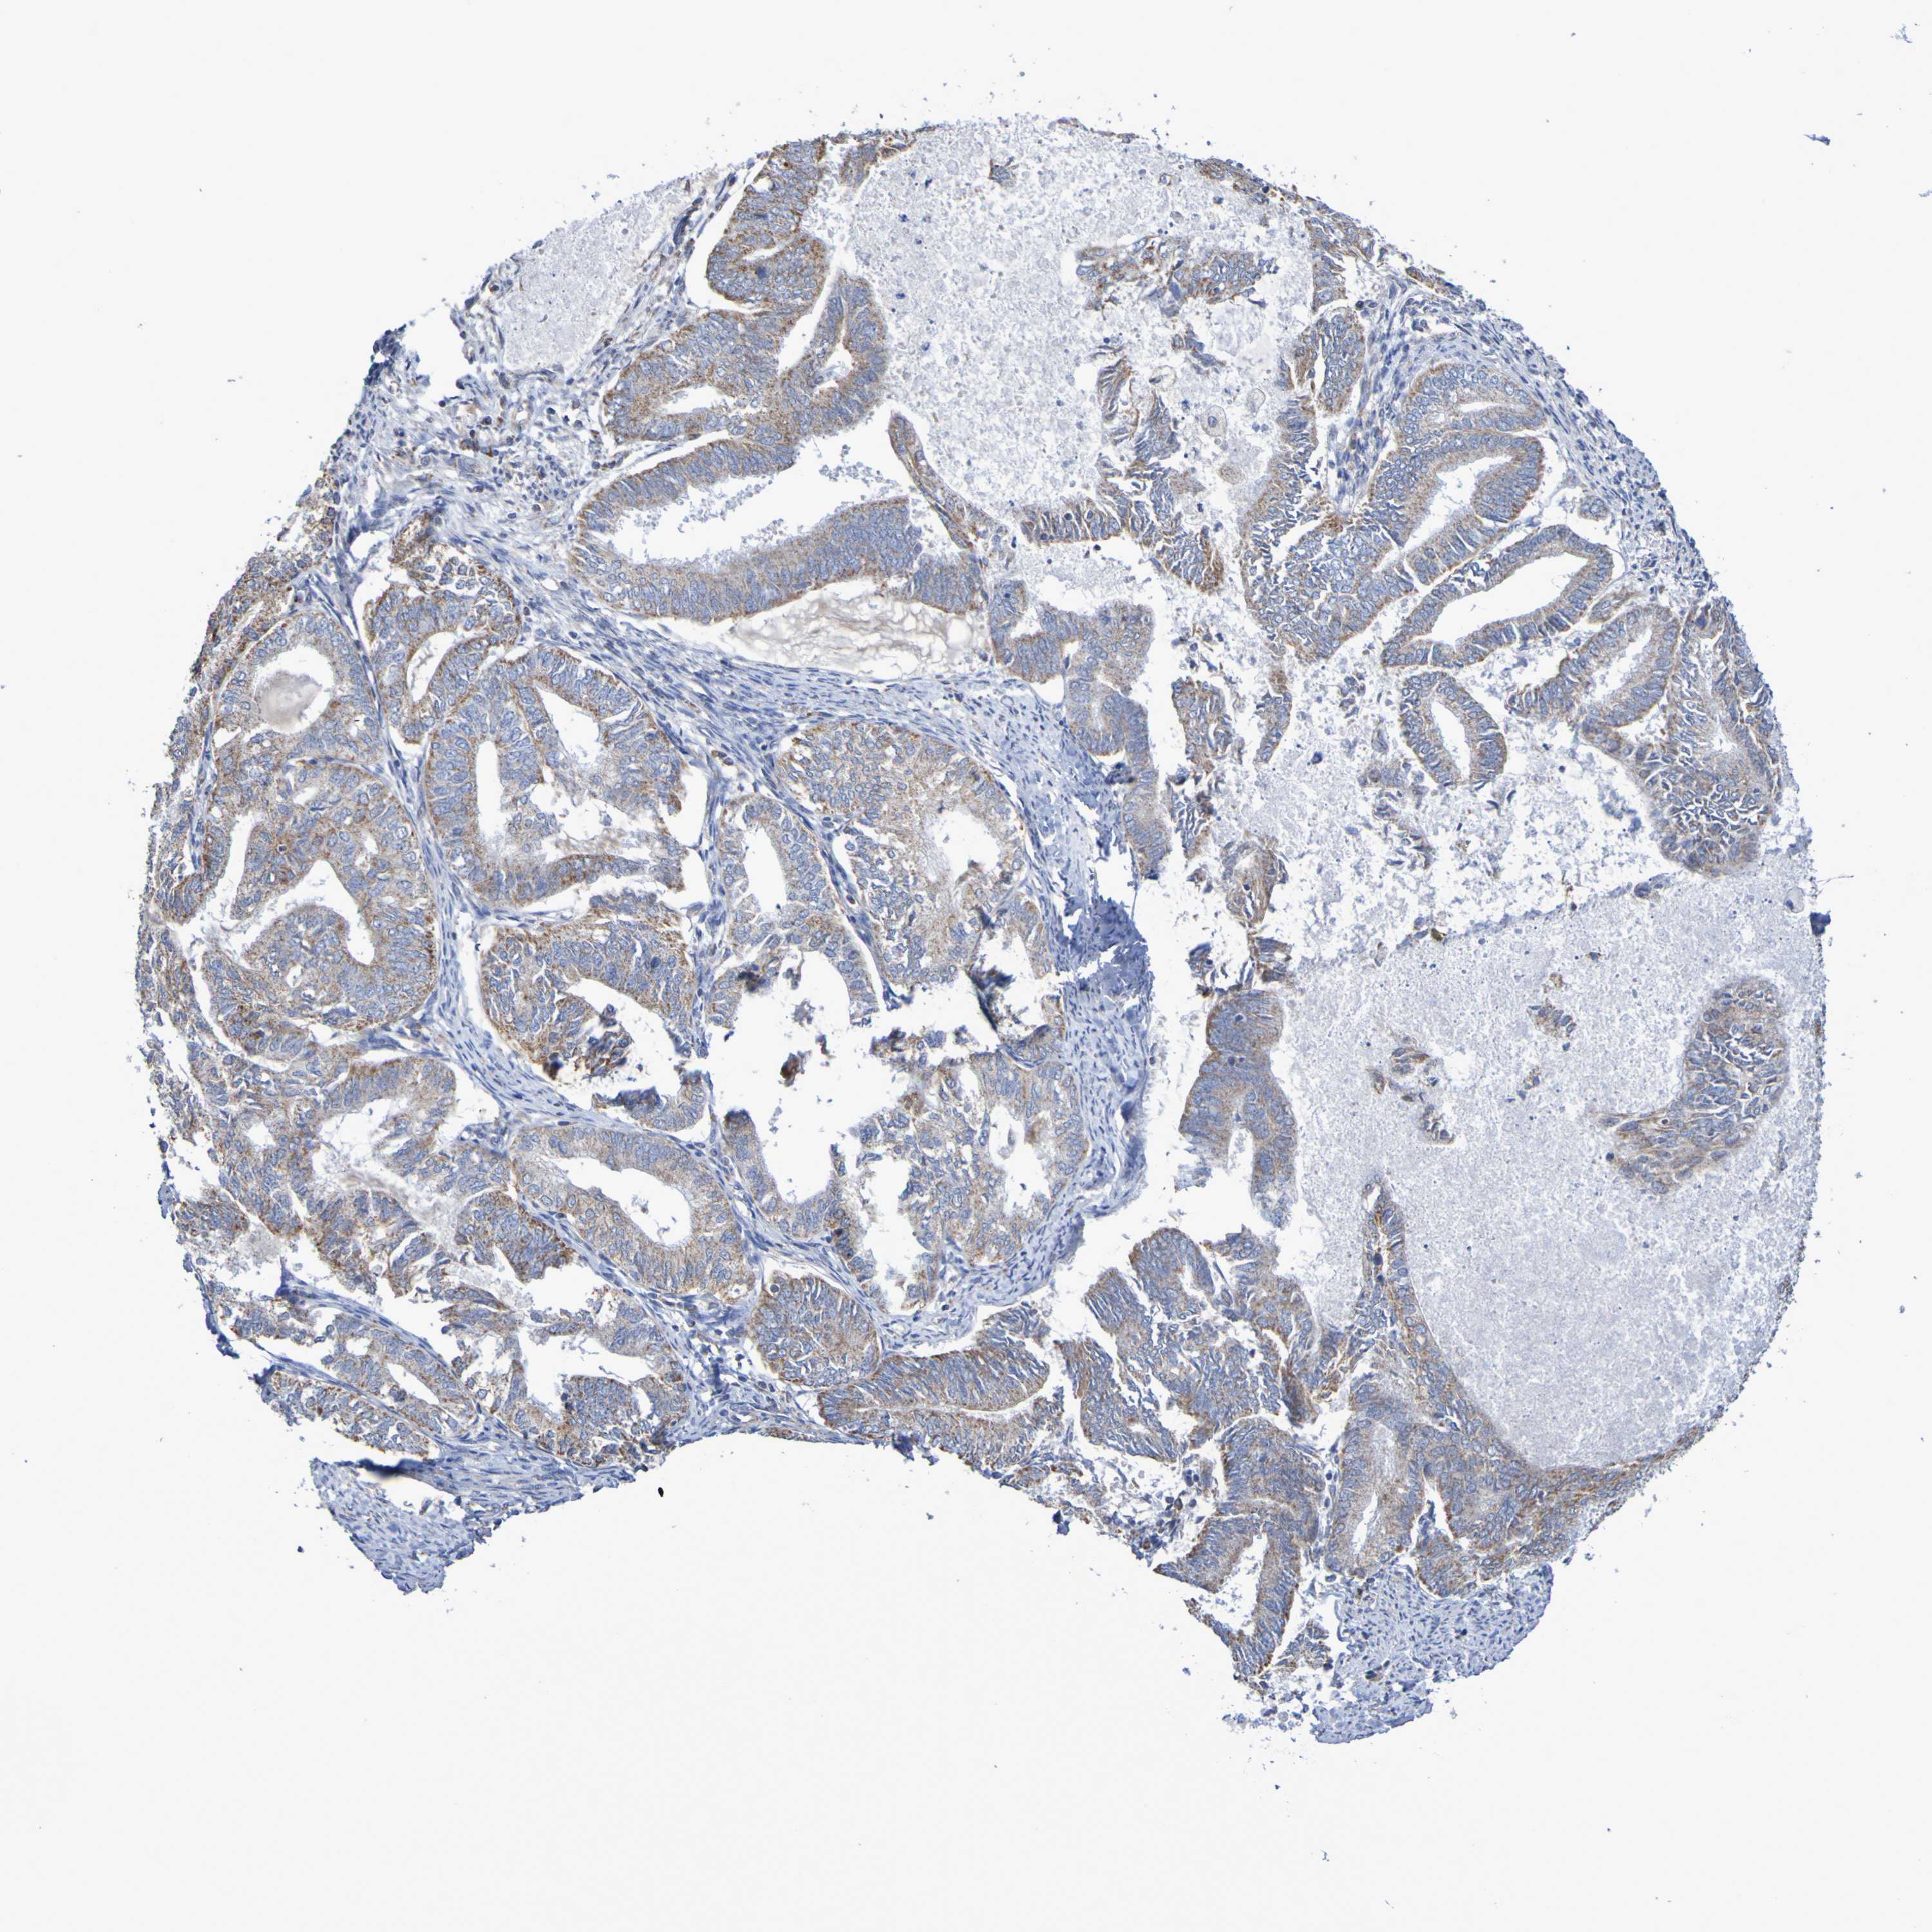

ENDOMETRIAL CANCER - Protein expressioni

A mouse-over function shows sample information and annotation data. Click on an image to view it in a full screen mode. Samples can be filtered based on level of antibody staining by selecting one or several of the following categories: high, medium, low and not detected. The assay and annotation is described here.

Note that samples used for immunohistochemistry by the Human Protein Atlas do not correspond to samples in the TCGA dataset.

Antibody stainingi

Antibody staining in the annotated cell types in the current human tissue is reported as not detected, low, medium, or high, based on conventional immunohistochemistry profiling in selected tissues. This score is based on the combination of the staining intensity and fraction of stained cells.

Each image is clickable and will lead to virtual microscopy that enables deeper exploration of all samples and also displays staining intensity scores, fraction scores and subcellular localization as well as patient and tissue information for each sample.

Antibody HPA001397

Antibody HPA012497

Staining

High

Medium

Low

Not detected

Intensity

Strong

Moderate

Weak

Negative

Quantity

>75%

75%-25%

<25%

None

Location

Nuclear

Cytoplasmic/membranous

Cytoplasmic/membranous,nuclear

Adenocarcinoma, NOS